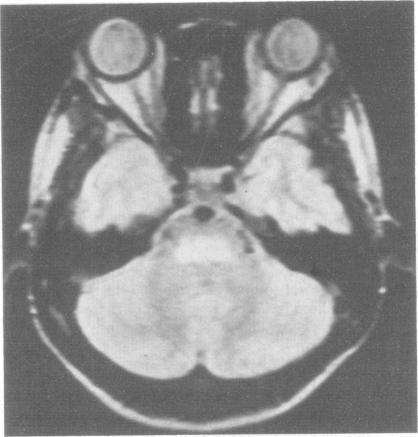

Magnetic resonance imaging (MRI) was performed in two patients in whom a clinical diagnosis of central pontine myelinolysis (CPM) had been made. MRI showed lesions in the pons in both cases about 2 years after the illness, at a time when the spastic quadriparesis and pseudobulbar palsy had recovered. The persisting abnormal signals in CPM are likely to be due to fibrillary gliosis. Persistence of lesions on MRI means that the diagnosis of CPM may be electively, after the acute illness has resolved.